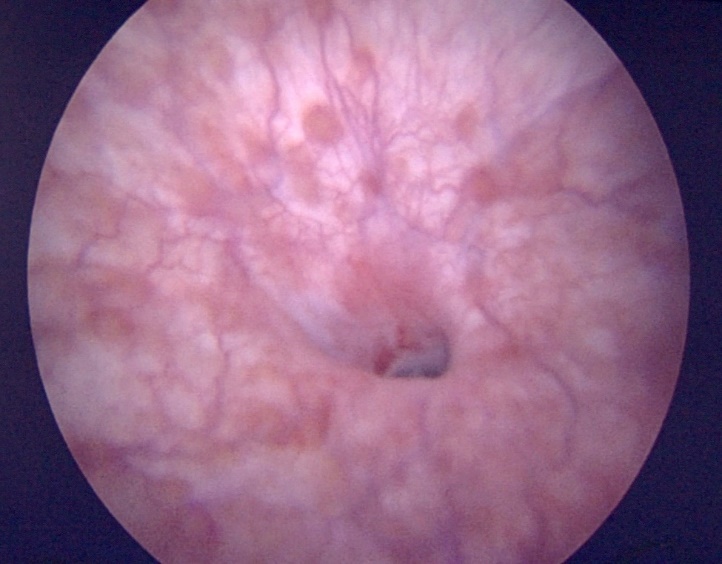

La cistoscopia cumple un rol fundamental en el estudio de toda paciente con FVV (Figura 19). Los elementos a evaluar son: número de trayectos fistulosos, tamaño de el o los orificios a nivel vesical, ubicación del orificio y su relación con los meatos ureterales y el cuello vesical, presencia de cuerpo extraño como malla o material de sutura y características generales del tejido vesical que rodea la fístula. Si no se logra visualizar la FVV en la cistoscopía, la maniobra de avanzar una guía a través del ostium vaginal puede ser de utilidad. En caso de sospecha de fístula por tumor pelviano, se recomienda tomar biopsia fría.